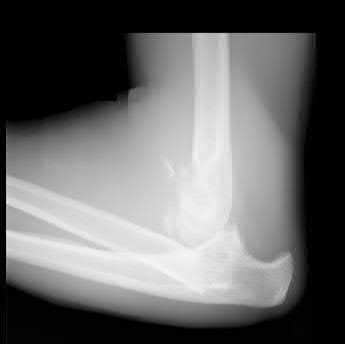

A 26-year-old male sustains an elbow injury after a fall from a skateboard resulting in valgus and supination forces across the left elbow. A CT scan of the left elbow is shown in Figures A through D. This fracture pattern is most commonly associated with what other traumatic elbow pathology?

The clinical presentation is consistent with a coronoid tip fracture. This fracture pattern is associated with a radial head fracture and posterolateral ulnohumeral dislocation - together making up the terrible triad injury.

A terrible triad injury is the result of a valgus and supination injury and involves posterolateral elbow dislocation or lateral collateral ligament injury, radial head fracture, and fracture of the coronoid process. The elbow may dislocate postero-laterally with the anterior bundle of the MCL intact, but if the MCL is injured it is typically the last structure to fail. The coronoid fracture is typically a small fragment isolated to the tip. This is a result of a posteriorly directed force driving the coronoid into the trochlea prior to posterior elbow dislocation. CT scan is a useful modality when small or comminuted fragments are difficult to visualize on plain radiographs.

Figures A through D show consecutive 2.00 mm sagittal CT reformats demonstrating a small coronoid fracture fragment which was addressed with suture fixation.